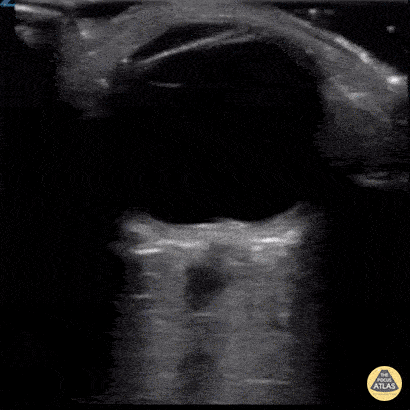

Orbital - Papilledema

A 27 year-old female presented to the emergency department with a two week history of headache, posterior eye pain, and visual changes. A bedside ultrasound was performed demonstrating a dilated optic nerve sheath and a bulging optic disc protruding into the posterior chamber consistent with papilledema. A CT of the head was unremarkable and an LP was performed with opening pressure of 36 mmH2O consistent with intracranial hypertension. Image courtesy of Dr. Amir Aminlari Ultrasound Fellowship Director, University of California San Diego